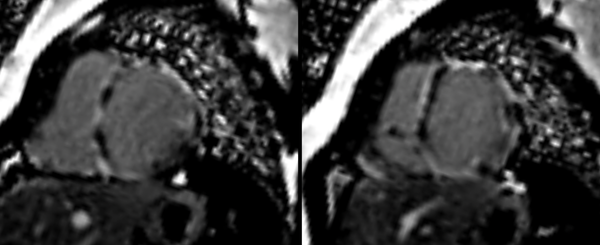

A common clinical presentation of LBBB induced cardiomyopathy is described in this post. It is always dilemma that if LBBB is cause or effect of dilated cardiomyopathy. However CMR can help in differentiating it from other causes and also in predicting response to device therapy. Utilise CMR to the fullest.

A lecture describing the role of CMR in the various non-ischemic cardiomyopathies